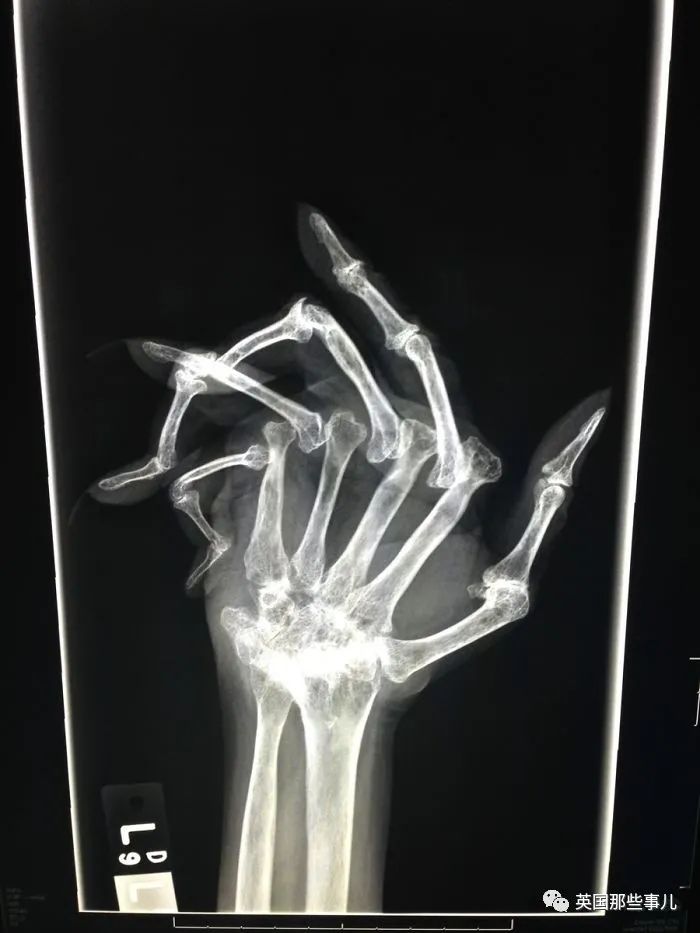

患有晚期類風濕關(guan) 節炎的手掌